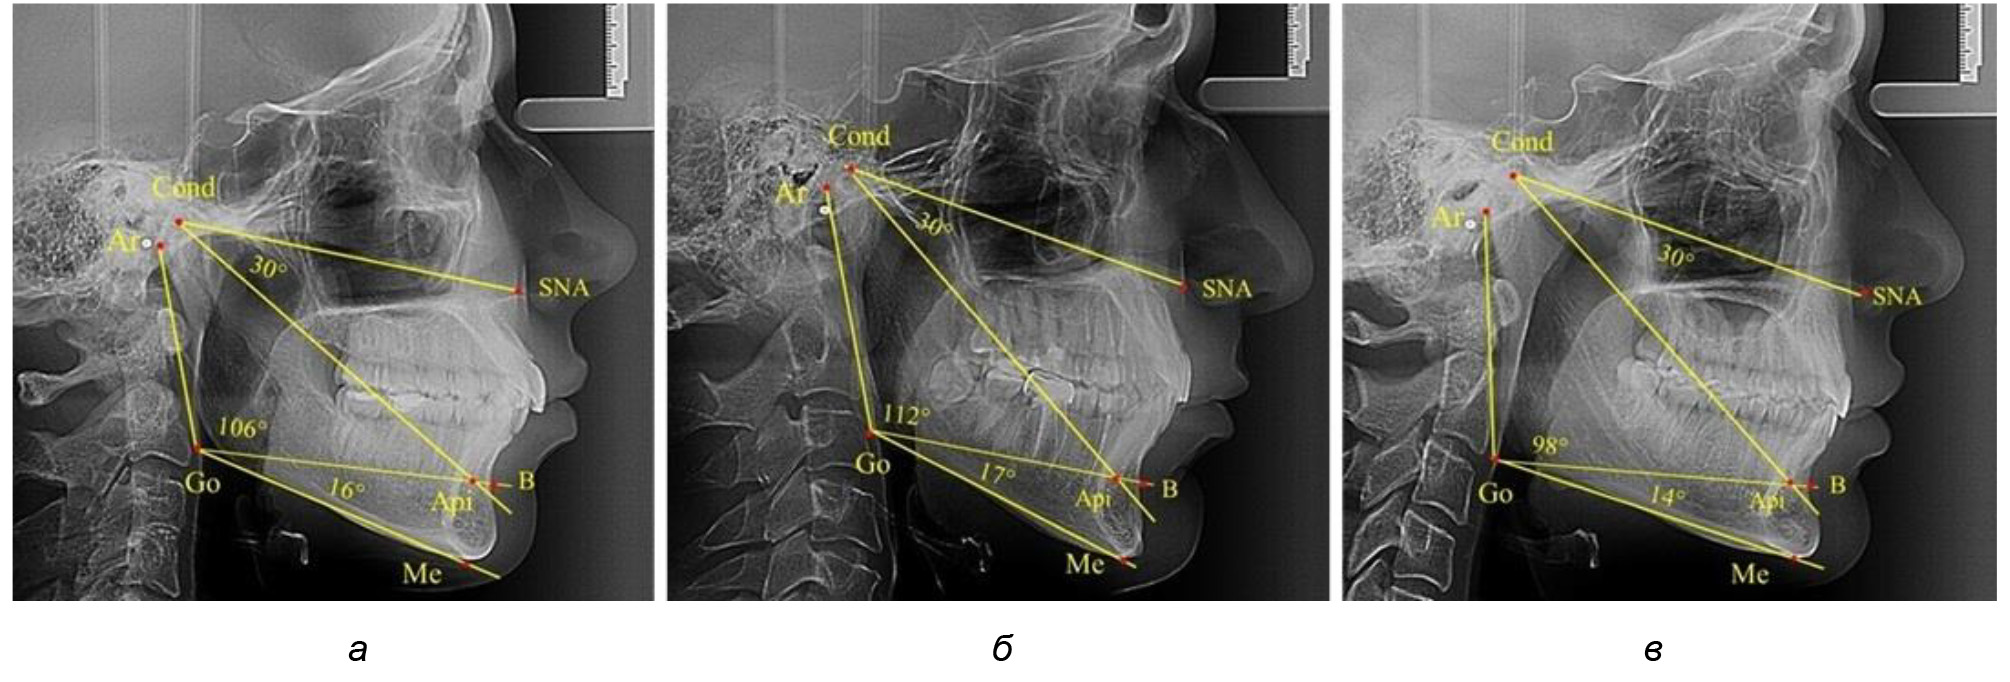

В результате исследования телерентгенограмм людей в периоде сформированного постоянного прикуса выявлено, что величина угла гнатической части лица SNA-Cond-Api в среднем по группе составил (29,96 ± 0,84)°. При анализе рентгенограмм с разными типами нижнечелюстного угла Ar-Go-Me достоверных различий величины угла гнатической части лица нами не отмечено и при физиологической окклюзии показатели варьировали от 27 до 33°, что определяло оптимальные параметры гнатического отдела лица.

В то же время нижнечелюстной угол варьировал в широких пределах, в частности от 112 до 127°, и его средние значения при физиологическом прикусе составляли (120,57 ± 1,43)°. При этом составляющие части нижнечелюстного угла имели различия. Так, показатель угла Ar-Go-Api варьировал от 110 до 117°, при средних значениях – (107,12 ± 1,73)°. Величина угла Api-Go-Me составляла в среднем (13,56 ± 1,09)° при минимальных значениях 6° и максимальном показатели 19°. Анализируя параметры нижнечелюстного угла на телерентгенограммах с различными типами нижнечелюстного угла, выявлено, что у людей с нейтральными типами угла (в пределах от 119 до 123°) средний показатель был (121,83 ± 0,62)°. Величина угла Ar-Go-Api составила (107,89 ± 1,62)°, а угол Api-Go-Me был (13,83 ± 1,12)°.

При вертикальном типе нижнечелюстного угла его средние значения составили (125,51 ± 0,44)°, и достоверно отличалась от показателей людей с нейтральными значениями нижнечелюстного угла. Величина угла Ar-Go-Api составила (115,49 ± 2,14)°, а угол Api-Go-Me был (13,97 ± 1,26)°.

Для горизонтального типа роста было характерно достоверное р ˂ 0,05 уменьшение нижнечелюстного угла до (115,57 ± 0,56)°. Величина угла Ar-Go-Api составила (102,71 ± 1,62)°, а угол Api-Go-Me был (12,86 ± 0,74)° (рис. 3).

Рис. 3. Особенности ТРГ при нейтральном (а), вертикальном (б) и горизонтальном (в) типе угла нижней челюсти в постоянном прикусе

Таким образом, вне зависимости от величины нижнечелюстного угла, показатели угла гнатической части лица были в пределах 30°, что может расцениваться в качестве оптимального физиологического показателя параметров гнатической части лица. Анализ ТРГ проведен у 31 ребенка в различные периоды дентального онтогненеза, включая прикус молочных зубов и различные группы прорезывания постоянных зубов.